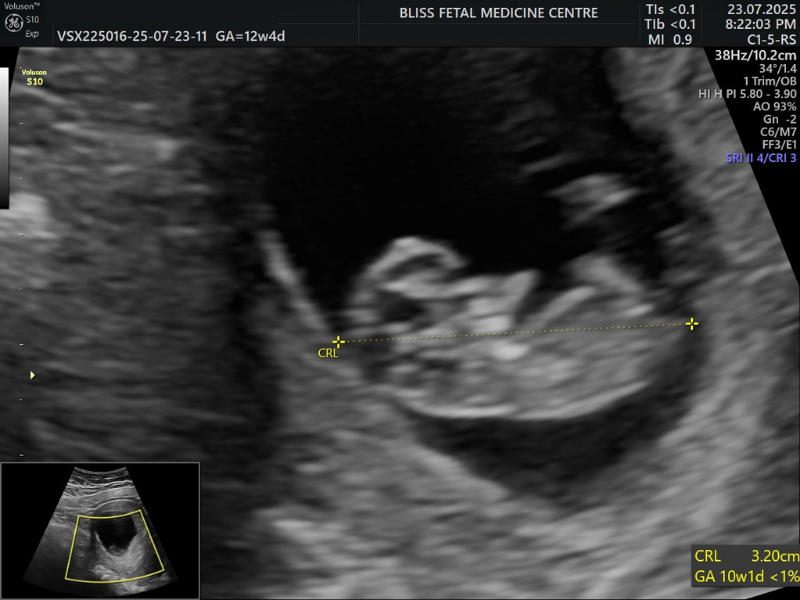

2. First Trimester (NT-NB) Scan

A Nuchal Translucency/Nasal Bone (NT-TB) Scan helps assess the risk of the baby having specific chromosomal abnormalities. The NT scan measures the space filled with fluid behind the neck of your unborn baby, while the NB scan helps determine the absence or presence of the nasal bone, which can indicate potential chromosomal issues.

When Is It Performed?

- It is performed between 11 and 14 weeks of pregnancy in the first trimester.

- It is recommended when a woman’s age, family history, lifestyle, etc, can increase risks.

- It can also be recommended if the previous tests show potential risks.